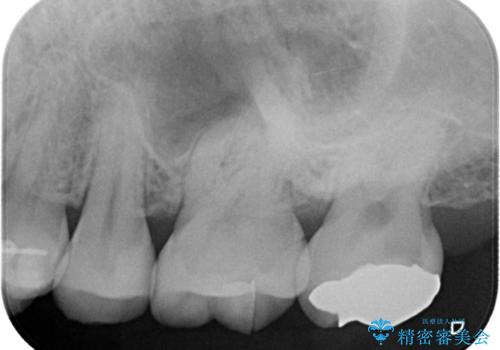

- レントゲンにて昔入れたインレーの下に虫歯が見つかった患者様です。

歯髄に近接する虫歯でしたが、根管治療は必要なくクラウンにて修復を行うことができました。